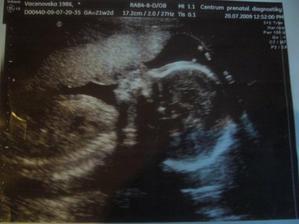

Dneska 20.7.jsme byli na screeningu v II.trimestru vše je v požádku,miminko roste jak má má 350g a 20cm a v bříšku se schovává další holčička už se na ní všichni moc těšíme a bude se jmenovat Sofinka.

Na velký ulz do Brna do Heliosu jdeme 6.8.Tak Sofinka na nás prďákovala a pořád si zakrývala obličejíček,ale to nevadí i tak to bylo krásný